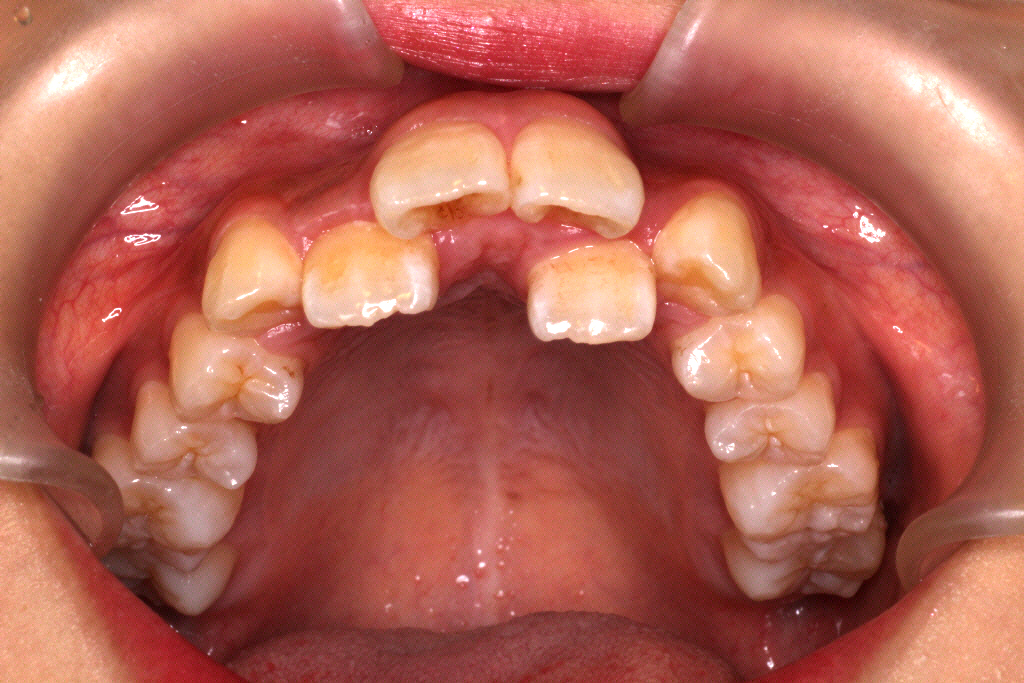

51枚中27枚目くらいでマウスピースが合わなくなった9ヶ月後のお口の中の状態です。

患者さんの左上の1番目と3番目の間に隙間ができてきて、2番目の歯が少し見えるようになりました。

まだまだ並ばせていかないといけないので、リファイメント1回目(マウスピースの作り直し)を行いました。